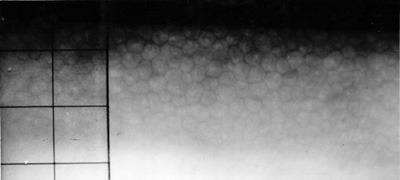

Foto 4 - Endotelio del OD afectado

Foto 5 Endotelio del OI

Endotelio OD :2.300 cel/mm2 con leve pleomor smo y polimegatismo - Endotelio OI: 400 cel/mm2. con pleomor smo y polimegatismo (Fotos No14 y 15)

Foto 14- Endotelio en el OD con 2.300cl/mm2

Foto 15 -Endotelio en el OI con 400cl/mm2>.